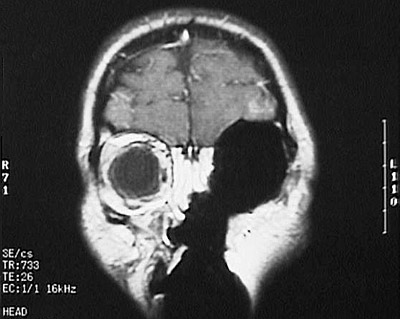

These MRI scans of the head reveal an irregular enhancing area of

mucormycosis

on the left. There is overlying

soft tissue swelling

. One of the views below indicate the result of treatment of this condition--radical surgical excision.